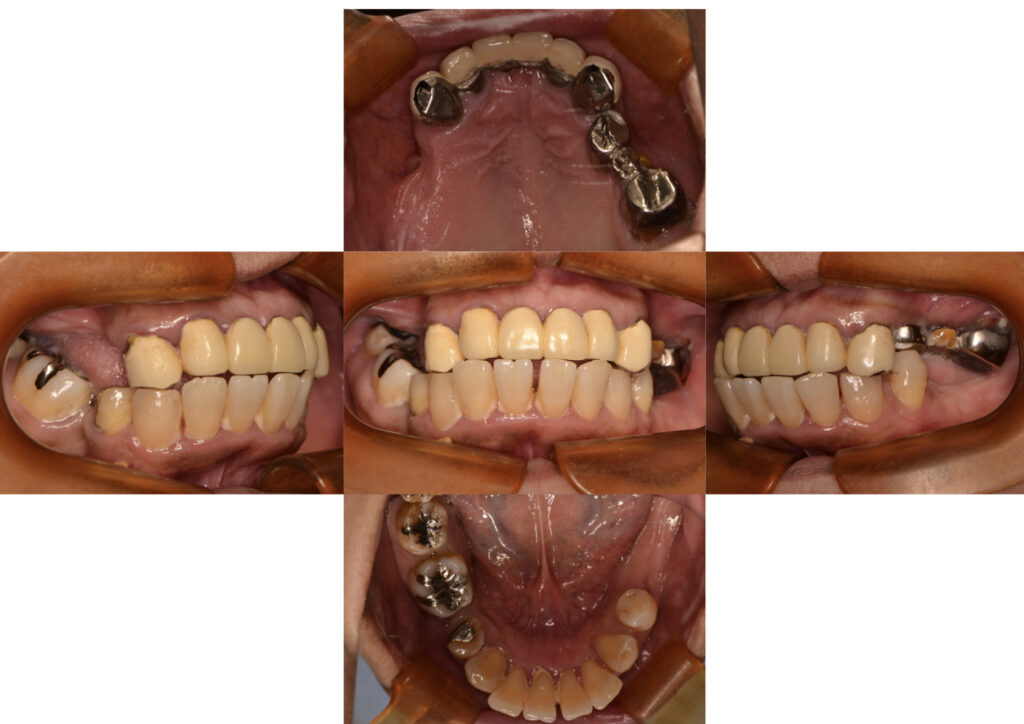

60代女性。初診時の口腔内写真、臼歯部の咬合崩壊と前歯部のフレアーアウトを起こしています。